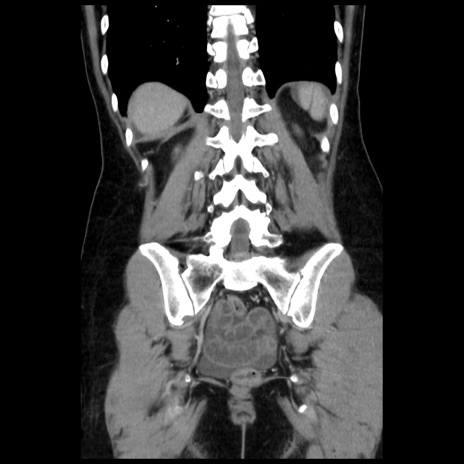

症例10(冠状断像)

【症例】 50歳代女性

【主訴】 腹痛

【現病歴】前日生レバーを食べた。今朝に排便あり。 昼前に突然発症の腹痛を生じ、当院救急外来を受診した。

【既往歴】 子宮筋腫にてで子宮全摘後

【身体所見】 意識清明、腹部:平坦、軟、下腹部やや左を中心に圧痛・反跳痛あり、筋性防御あり

【データ】WBC 7800、CRP 0.07